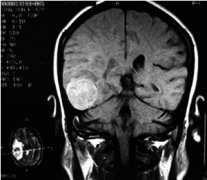

蛛網(wǎng)膜囊腫,屬于先天性良性腦囊腫病變,是由于發(fā)育期蛛網(wǎng)膜分裂異常所致。囊壁多為蛛網(wǎng)膜、神經(jīng)膠質(zhì)及軟腦膜,囊內(nèi)有腦脊液樣囊液。囊腫位于腦表面、腦裂及腦池部,不累及腦實(shí)質(zhì)。多為單發(fā),少數(shù)多發(fā)。本病多無(wú)癥狀,體積大者可同時(shí)壓迫腦組織及顱骨,可產(chǎn)生神經(jīng)癥狀及顱骨發(fā)育改變。本癥多見(jiàn)于兒童及青少年,男性較多,左側(cè)較右側(cè)多見(jiàn)。蛛網(wǎng)膜囊腫按病因不同可分為先天性和繼發(fā)性(外傷性及感染后)兩大類(lèi),按部位不同可分為顱內(nèi)型及脊髓型兩類(lèi)。